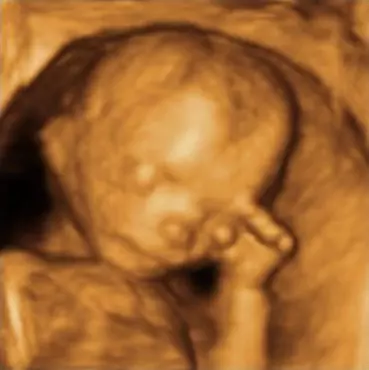

GINEKOLOŠKA ORDINACIJA ŠTEFO ĐURIĆ, DR. MED., SPECIJALISTGINEKOLOGIJE I OPSTETRICIJE I PEDIJATRIJSKA ORDINACIJA RUŽICA ĐURIĆ, DR. MED.,SPECIJALIST PEDIJATAR pružaju usluge 3D i 4D ultrazvuka za trudnice.

Usluge koje ova ordinaciju nudi su ginekološka i pedijatrijska ordinacija sa kompletnim pregledima i uslugom. Ordinacije nude usluge 3D/4D ultrazvuka i color dopplera i drugih zdravstvenih usluga u području ginekologije i pedijatrije.

3D i 4D ultrazvuk, usluge su koje pruža GINEKOLOŠKA ORDINACIJA ŠTEFO ĐURIĆ, DR. MED., SPECIJALISTGINEKOLOGIJE I OPSTETRICIJE I PEDIJATRIJSKA ORDINACIJA RUŽICA ĐURIĆ, DR. MED.,SPECIJALIST PEDIJATAR.